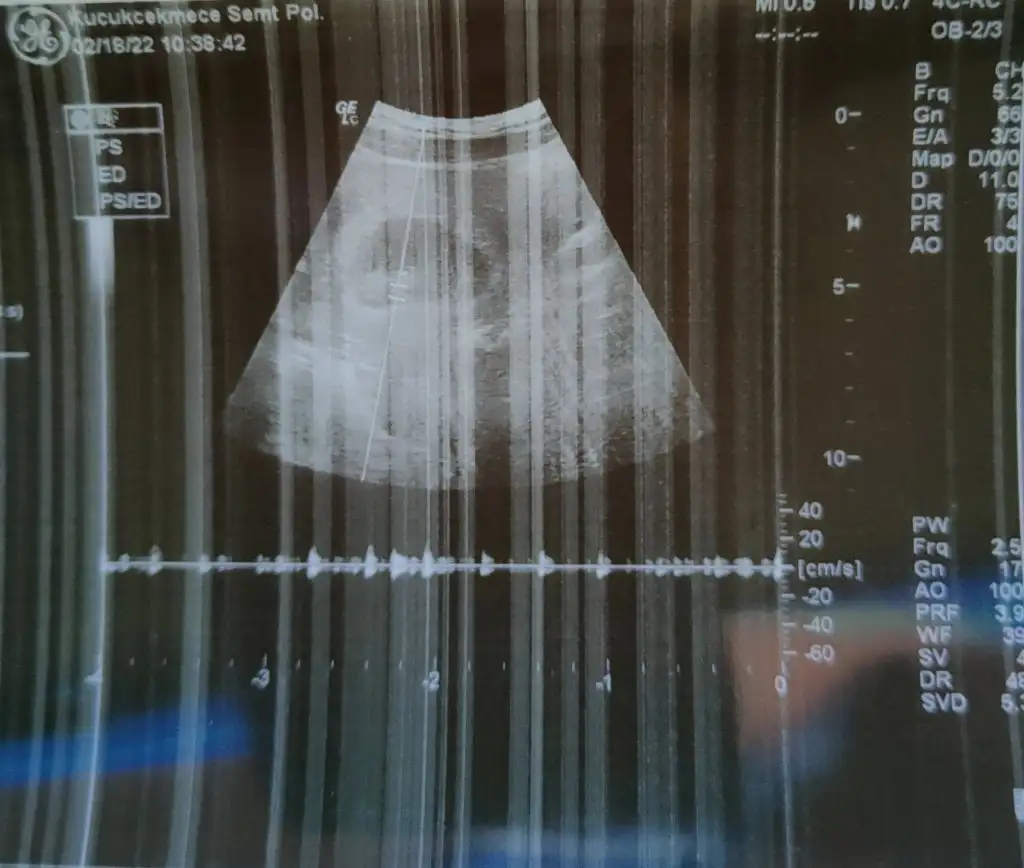

selam kızlar🤩bende bugün ilk muayeneme gittim.Ekim ayında kürtaj yaşadığım için,bunda erkenden sevinemedik,bilerek ilk kontrolü 8.haftaya aldım ki herşeyini göreyim diye.Cok şükür, herşey yolundaymis,çok sevindim 🌼8+4 çıktı ,boyu da 1.95 cm olmuş,tombalak görünüyor 🤣🤣hepimiz sağlıcakla kucağımıza alırız inşallah 🤲

selam kızlar🤩bende bugün ilk muayeneme gittim.Ekim ayında kürtaj yaşadığım için,bunda erkenden sevinemedik,bilerek ilk kontrolü 8.haftaya aldım ki herşeyini göreyim diye.Cok şükür, herşey yolundaymis,çok sevindim 🌼8+4 çıktı ,boyu da 1.95 cm olmuş,tombalak görünüyor 🤣🤣hepimiz sağlıcakla kucağımıza alırız inşallah 🤲Eki Görüntüle 3009068